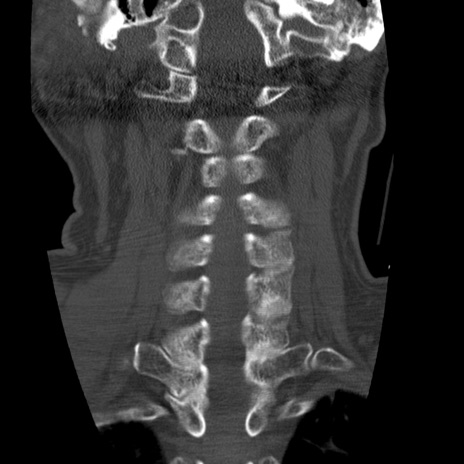

症例50 頚椎CT(冠状断像)

頚椎CT

横断像